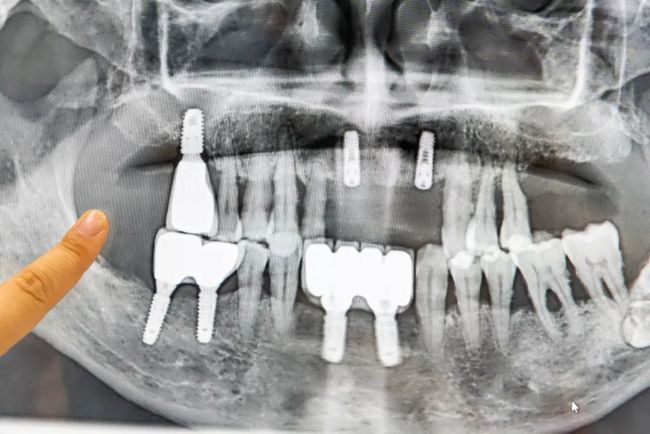

多颗缺失

种植后